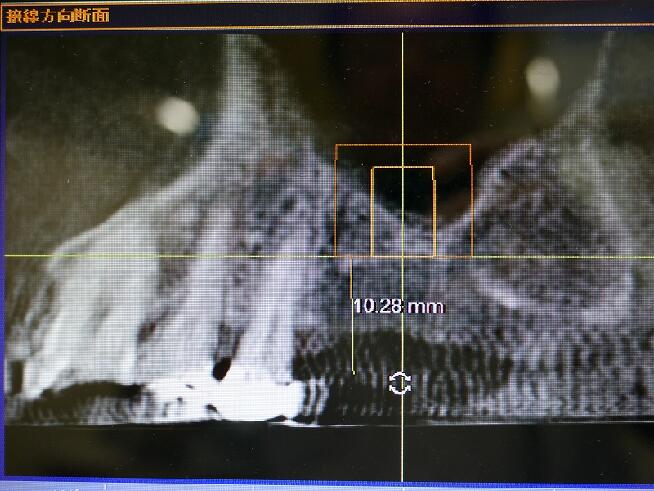

下記の症例では上顎のインプラントを実施するためCT(立体レントゲン)撮影致しました。

その部位の拡大エックス線像です

上顎には他の場所と違い上顎洞という頭を軽くするための空洞があり骨が2〜4ミリ程度しかなく、インプラントは大変困難です。